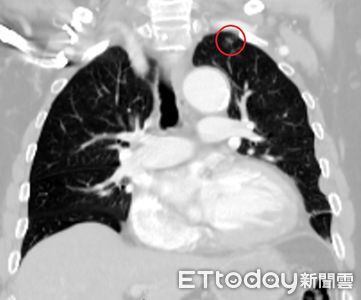

台中一名林姓男子因車禍造成肋骨多處骨折、胸腔積水,被送到醫院急救,結果就在醫師與影像醫學科團隊仔細檢視電腦斷層時,意外發現林男肺部有一個小於1公分的腫瘤,醫師進行手術搶命同時也切除腫瘤,最後病理報告也證實為肺腺癌,讓這個原本可能潛伏多年、毫無症狀的病灶,因車禍而被提早發現,讓男子免於癌王威脅。 《詳全文...》